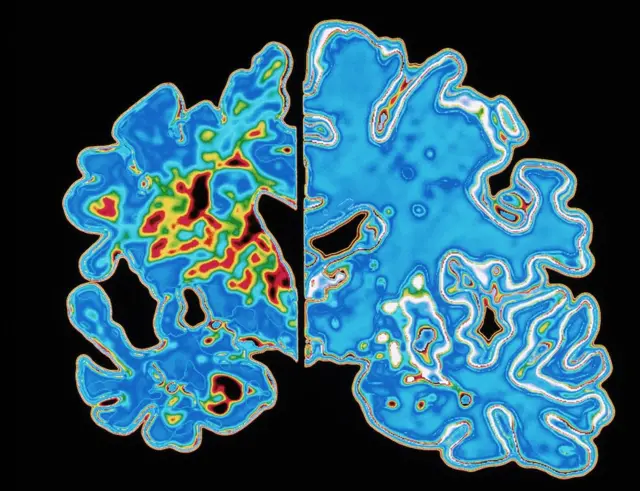

Fuente de la imagen, SPL

La demencia fue descrita por primera vez por el médico alemán Alois Alzheimer en 1906 tras realizar una autopsia a una mujer que había sufrido pérdida profunda de memoria.

Lo que encontró fue un cerebro muy reducido y anomalías en y alrededor de las células nerviosas.